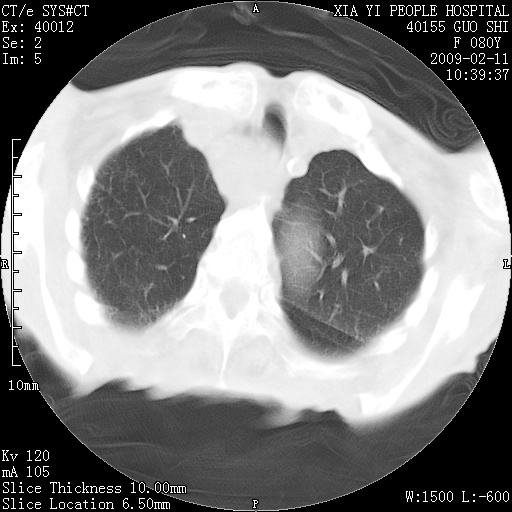

以下是引用随光逐影在2009-2-16 16:34:00的发言:[br]1)考虑右前纵隔皮样囊肿。2)双侧少量胸腔积液。

以下是引用zjzjr在2009-2-16 17:30:00的发言:[br]支持囊性畸胎瘤 双侧少量胸腔积液。